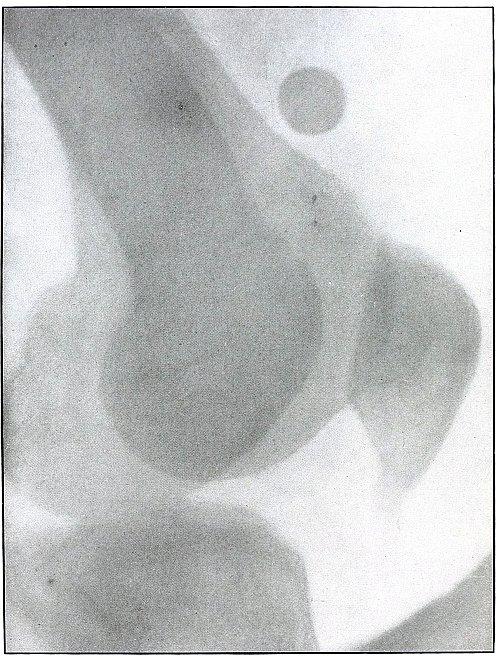

| 59. |

Gunshot wound, knee |

128 |